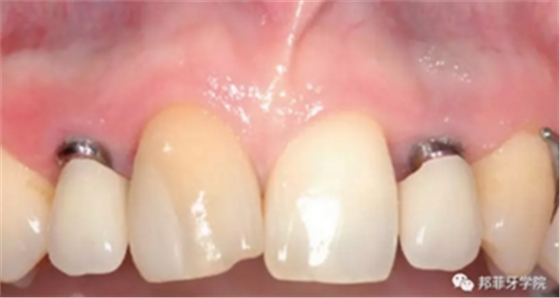

圖 11:植入10周后口內(nèi)情況

圖 12:椅旁制備臨時(shí)冠